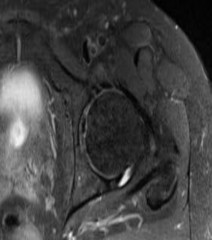

Question 10

A 55-year-old carpenter presents with right shoulder pain and weakness after attempting to lift a heavy tool box. On physical examination, he demonstrates a positive drop-arm test and profound weakness with active abduction in the scapular plane. An MRI confirms a massive, retracted tear of the supraspinatus and infraspinatus tendons. Fatty infiltration of these muscles is graded. Which classification system is most commonly used to grade fatty infiltration of the rotator cuff muscles on imaging?

Explanation

The Goutallier classification is used to quantify the amount of fatty infiltration of the rotator cuff muscles, originally described on CT but now widely adapted for MRI. High grades of fatty infiltration (Goutallier 3 and 4) are associated with poor functional outcomes and higher re-tear rates following surgical repair.